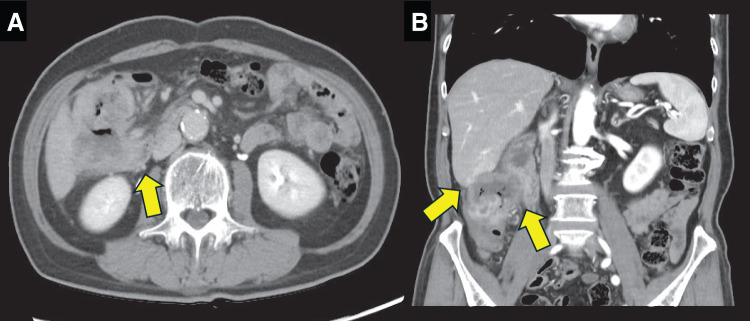

Case presentation: The patient was a 76-year-old man who presented with a chief complaint of right abdominal pain and weight loss of 12 kg over the past month. Colonoscopy revealed the entire circumference of a type 2 tumor in the ascending colon. Preoperative computed tomography showed a 12 cm mass lesion with wall thickening in the ascending colon which was also invading the second portion of the duodenum. MSI-H/dMMR was negative. RHPD and partial hepatectomy were performed with open surgery because of a preoperative diagnosis of clinical T4b (duodenum and liver) N1bM0 stage IIIc cancer. Although grade 2 adverse effects, which delayed gastric emptying was observed during the patient's postoperative course, the patient's condition resolved through conservative therapy. Oral intake started on postoperative day 17, and the patient was discharged on postoperative day 25. Capecitabine plus oxaliplatin was administered as adjuvant chemotherapy for 6 months. Hematoxylin and eosin staining revealed moderately differentiated adenocarcinoma invading the duodenum and liver. The patient was diagnosed as pathological T4b (duodenum and liver) N1bM0 stage IIIc cancer. No recurrence was noted up to 40 months after the surgery.